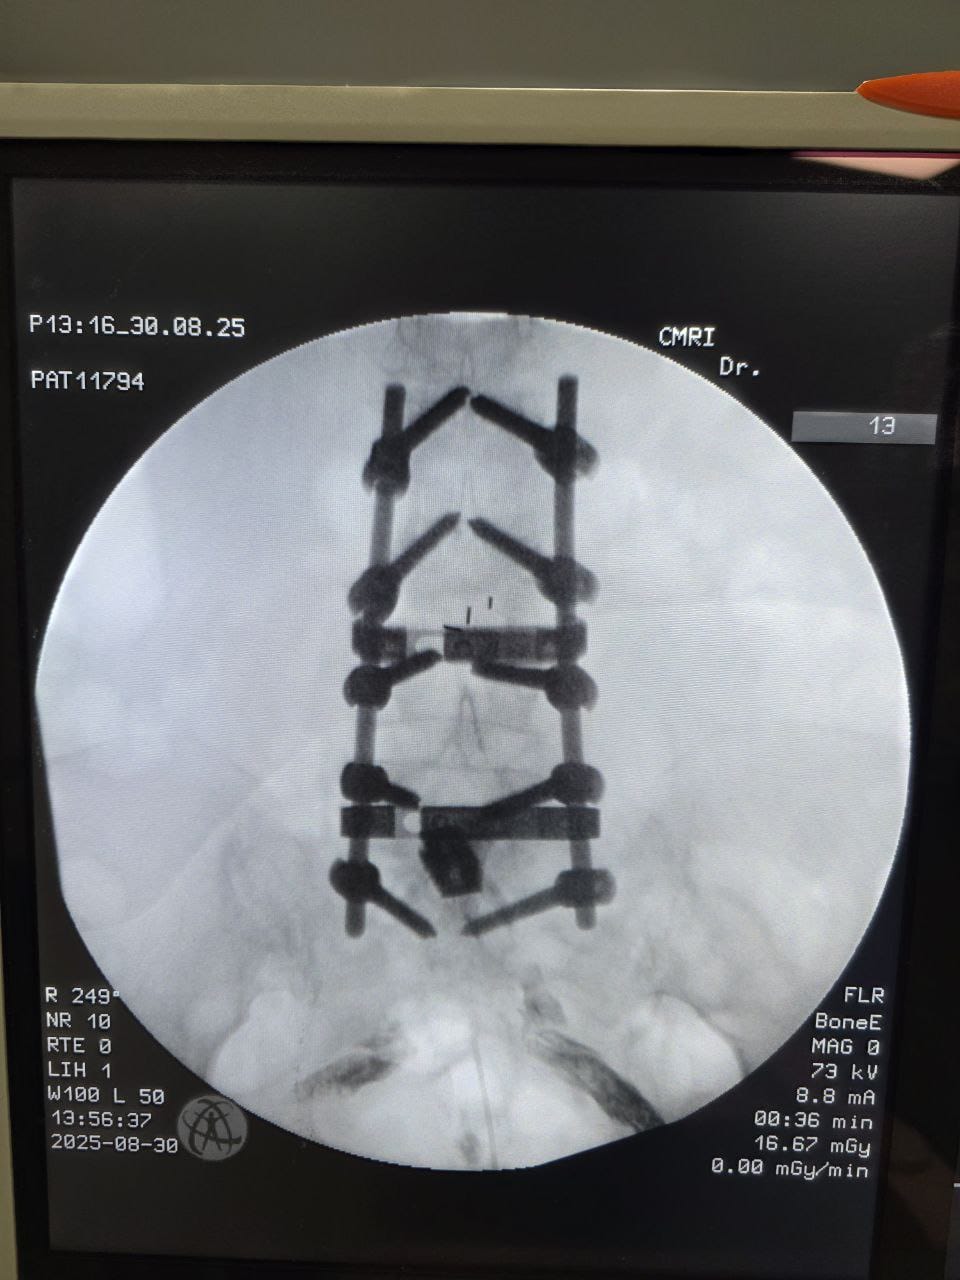

Struggling with chronic pain? Get advanced, personalised pain management from Dr. Manish De, one of Kolkata’s leading pain specialists. From knee pain, heel pain, low back pain, frozen shoulder, migraines, cancer pain to post-TKR persistent pain—Dr. De offers safe, evidence-based treatments across multiple locations: